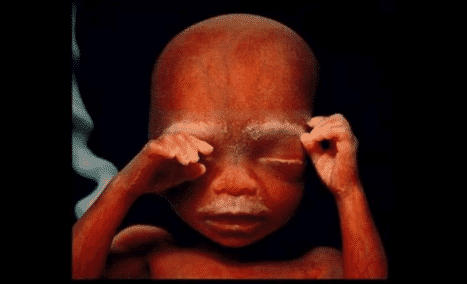

14. À 10 semaine, le foetus commence à utiliser ses mains